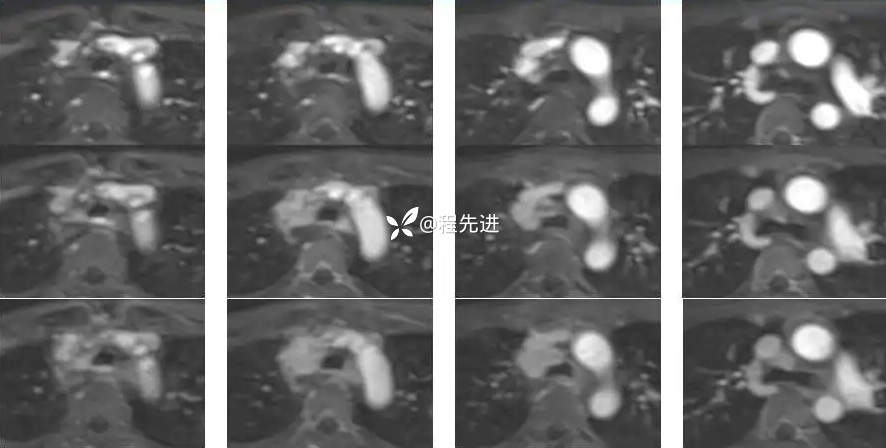

3期增强: